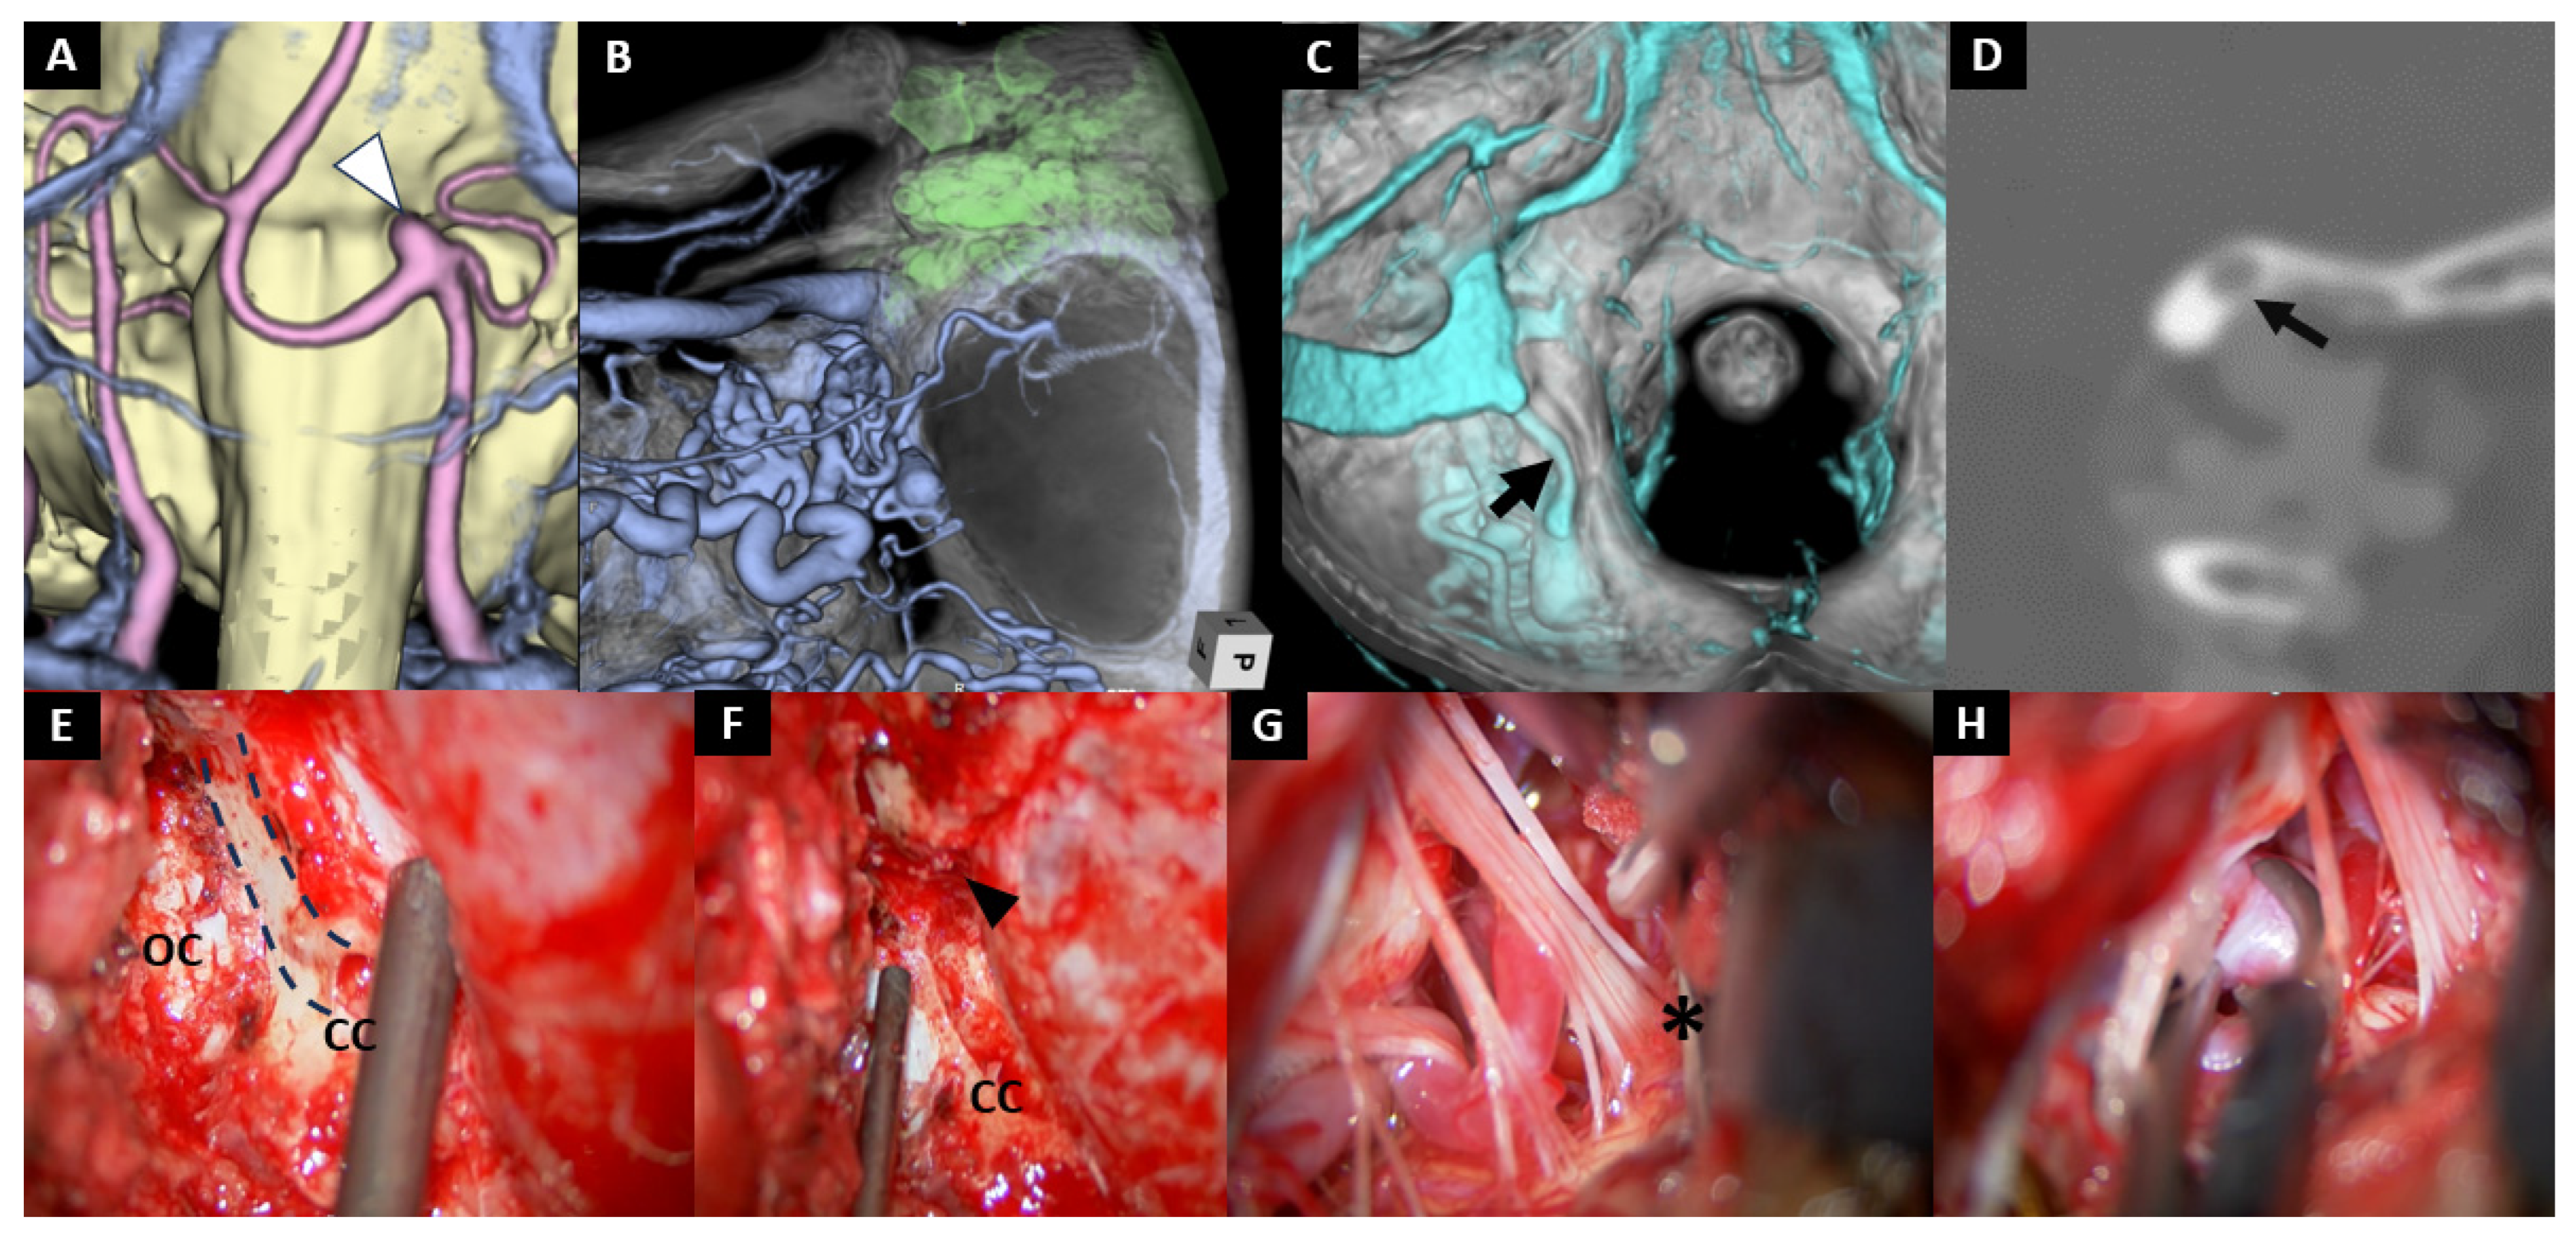

- Case No. 8

| 8 | 67 | M | saccular | BA-AICA (AICA-PICA) | 7 mm | Hybrid | Aspirin+ Heparin | - | - | + | - | 1 |